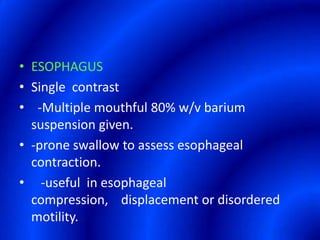

This document provides information about a barium swallow procedure. It begins with an introduction and overview of the embryology and anatomy of the pharynx and esophagus. It then describes the procedure itself, including preparation, technique, views obtained, and indications. Specific conditions that may be examined include pharyngeal and esophageal webs, foreign body impaction, scleroderma, dysphagia, mediastinal masses, and carcinoma. Diagrams are provided to illustrate normal anatomy and various pathological findings.